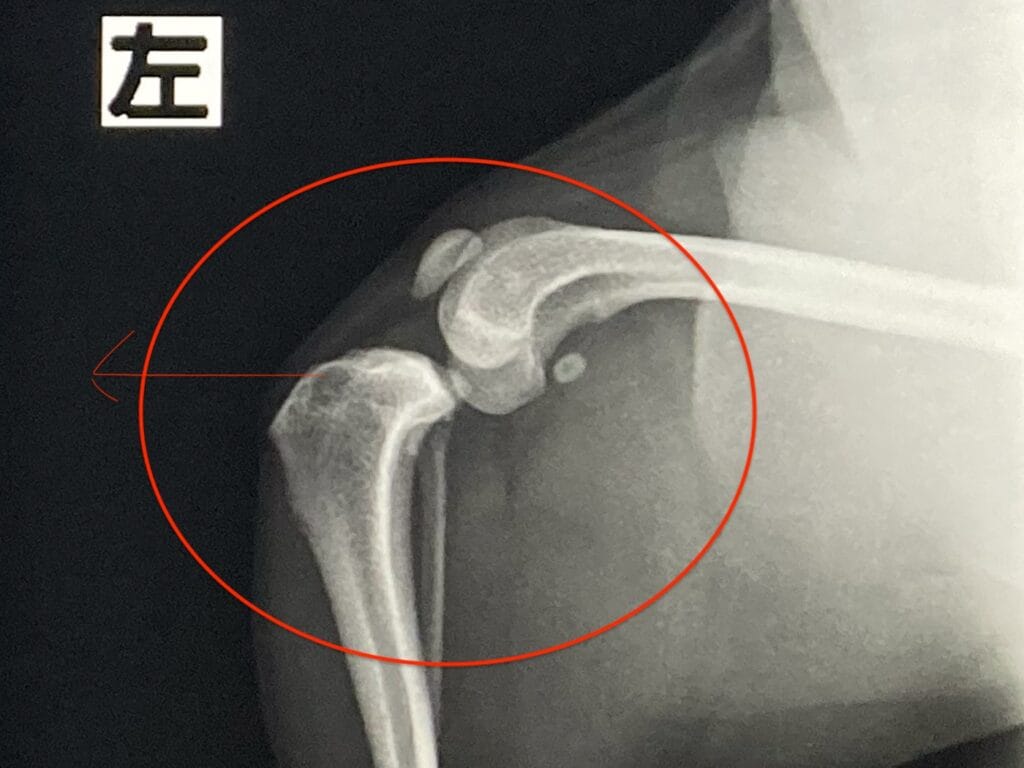

整形外科的検査とレントゲン検査の結果、左側の前十字靱帯断裂とパテラグレード4と診断しました。

前十字靭帯とは

膝関節内で大腿骨(太ももの骨)と脛骨(すねの骨)を結ぶ太い靱帯があり、脛骨(すねの骨)が前方に移動するのを防ぎ、膝関節を安定させる働きをしています。

前十字靭帯が断裂すると脛骨(すねの骨)が前方に移動し、歩く際に支える力がなくなってしまい、そのため違和感などで片足歩行になる傾向があります。

パテラグレード4とは

膝蓋骨が常に脱臼しており、手で押しても元に戻らない状態です。

側面からの撮影